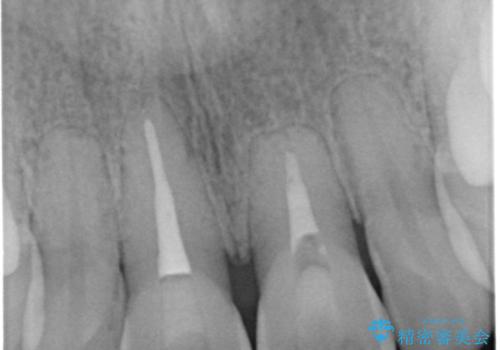

- 前歯の色が気になるとのことでご相談にいらした患者様です。診断の結果、前歯は2本とも失活していたために精密根管治療から治療を開始しました。根管治療後にウォーキングブリーチを行うことで歯の色をトーンアップさせました。患者様より周囲の歯も全体的に白くしたいとのご希望があったため、オフィスホワイトニングも併せて行いました。

ウォーキングブリーチ法とは歯の中に薬剤を入れて内側からホワイトニングを行う方法であるため、根管治療がされている歯のみ適応となります。生活歯(神経が生きている歯)に対してはオフィスホワイトニングやホームホワイトニングが有効です。